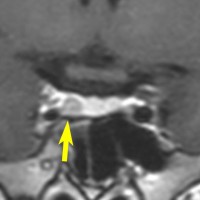

左は下垂体腺腫(緑の腫瘍)が内頚動脈に挟まれていることを示しています。

中央は手術前の下垂体腺腫で,視神経も正常下垂体も位置はわかりません。

右は手術翌日の画像です。黄色の矢印の先が残した正常下垂体組織です。桃色の矢印の先に視神経(視交叉)がはっきり見えています。術後の一時的な尿崩症がありました。クモ膜が残っているので髄液漏は生じませんでした。でも正常下垂体組織(黄色矢印)も視交叉も腫瘍に圧迫されてペラペラになっていますから,いつもうまく行くとは限りません。